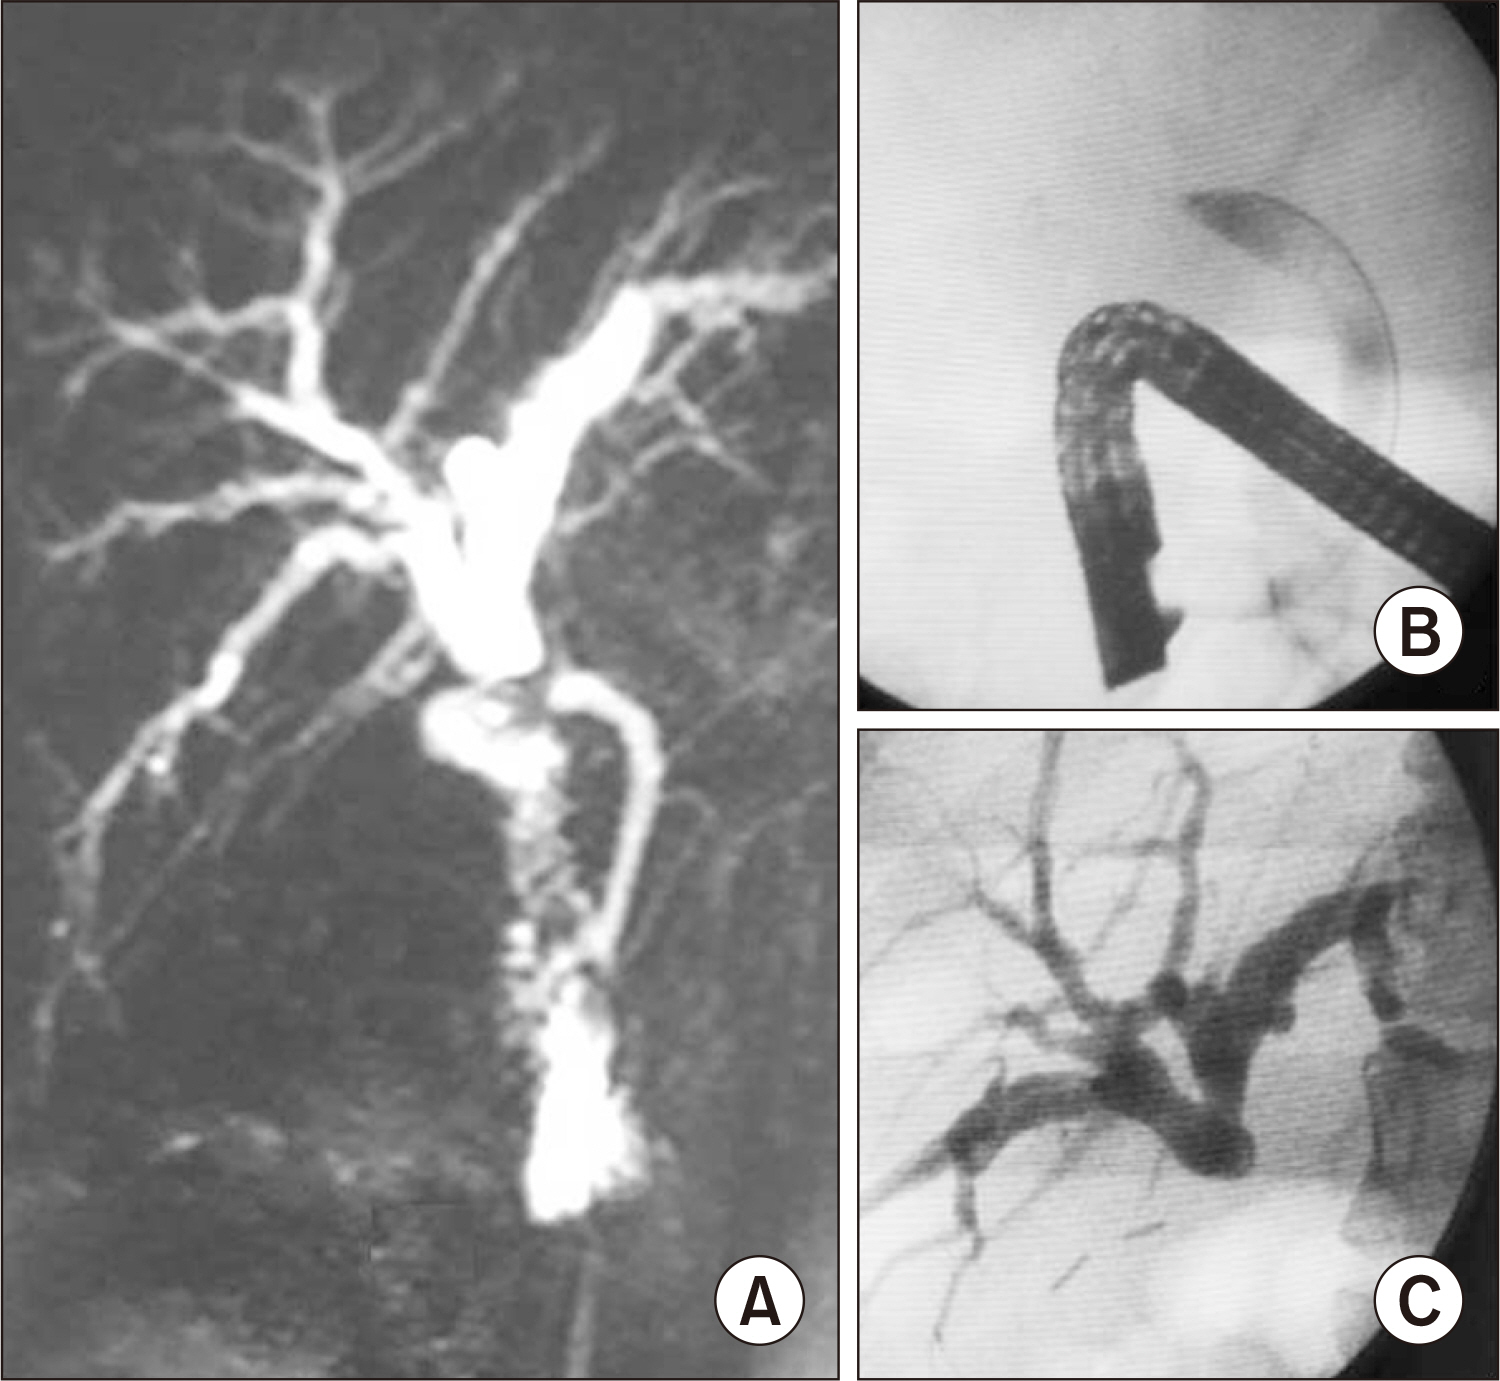

- Bile duct injuries are a serious issue, and their surgical treatment carries the risk of morbidity and mortality. In selected cases, non-surgical treatments are possible, even for total strictures. We outline the technique and results of using magnetic compression anastomosis (MCA) to treat post-cholecystectomy bile duct stricture (PCBDS), in two female patients. Initially, a bilio-cutaneous tract was established via external biliary drainage, followed by the positioning of both endoscopic and percutaneous biliary magnets. After their approximation and subsequent removal, a fully covered self-expandable metal stent (FCSEMS) was deployed across the stricture. The magnet coupling was successfully achieved within the first two weeks of placement. The FCSEMS was maintained for durations of 12 and 16 months. Follow-up durations were 28 and 15 months post-FCSEMS removal. Both patients remain asymptomatic, with normal laboratory and imaging studies, and no adverse events were reported. MCA proves to be a safe and effective method for treating selected cases of total PCBDS. However, further studies and long-term follow-up are required to fully assess the efficacy of this technique.

Article5. Jang SI, Cho JH, Lee DK. 2020; Magnetic compression anastomosis for the treatment of post-transplant biliary stricture. Clin Endosc. 53:266–275. DOI: 10.5946/ce.2020.095. PMID: 32506893. PMCID: PMC7280848.

Article6. Li Y, Sun H, Yan X, Wang S, Dong D, Liu X, et al. 2020; Magnetic compression anastomosis for the treatment of benign biliary strictures: a clinical study from China. Surg Endosc. 34:2541–2550. DOI: 10.1007/s00464-019-07063-8. PMID: 31399950.

Article7. Jang SI, Choi J, Lee DK. 2015; Magnetic compression anastomosis for treatment of benign biliary stricture. Dig Endosc. 27:239–249. DOI: 10.1111/den.12319. PMID: 24905938.

Article15. Jang SI, Rhee K, Kim H, Kim YH, Yun J, Lee KH, et al. 2014; Recanalization of refractory benign biliary stricture using magnetic compression anastomosis. Endoscopy. 46:70–74. DOI: 10.1055/s-0033-1358907. PMID: 24254385.

Article16. Jang SI, Do MY, Lee SY, Cho JH, Joo SM, Lee KH, et al. 2024; Magnetic compression anastomosis for the treatment of complete biliary obstruction after cholecystectomy. Gastrointest Endosc. 100:1053–1060.e1054. DOI: 10.1016/j.gie.2024.05.009. PMID: 38762041.

Article17. Do MY, Jang SI, Cho JH, Joo SM, Lee DK. 2022; Magnetic compression anastomosis for treatment of biliary stricture after cholecystectomy. VideoGIE. 7:253–255. DOI: 10.1016/j.vgie.2022.03.005. PMID: 35815159. PMCID: PMC9264143.

Article18. Ödemiş B, Başpınar B, Tola M, Torun S. 2022; Magnetic compression anastomosis is a good treatment option for patients with completely obstructed benign biliary strictures: a case series study. Dig Dis Sci. 67:4906–4918. DOI: 10.1007/s10620-022-07381-3. PMID: 35050430.